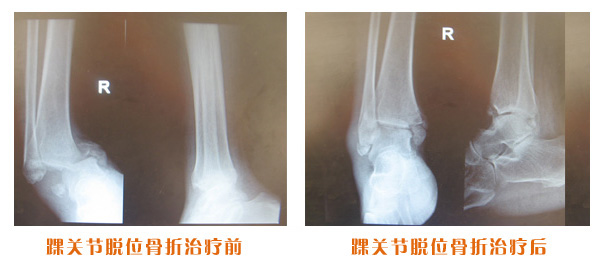

踝關(guān)節(jié)脫位骨折治療前后對(duì)比